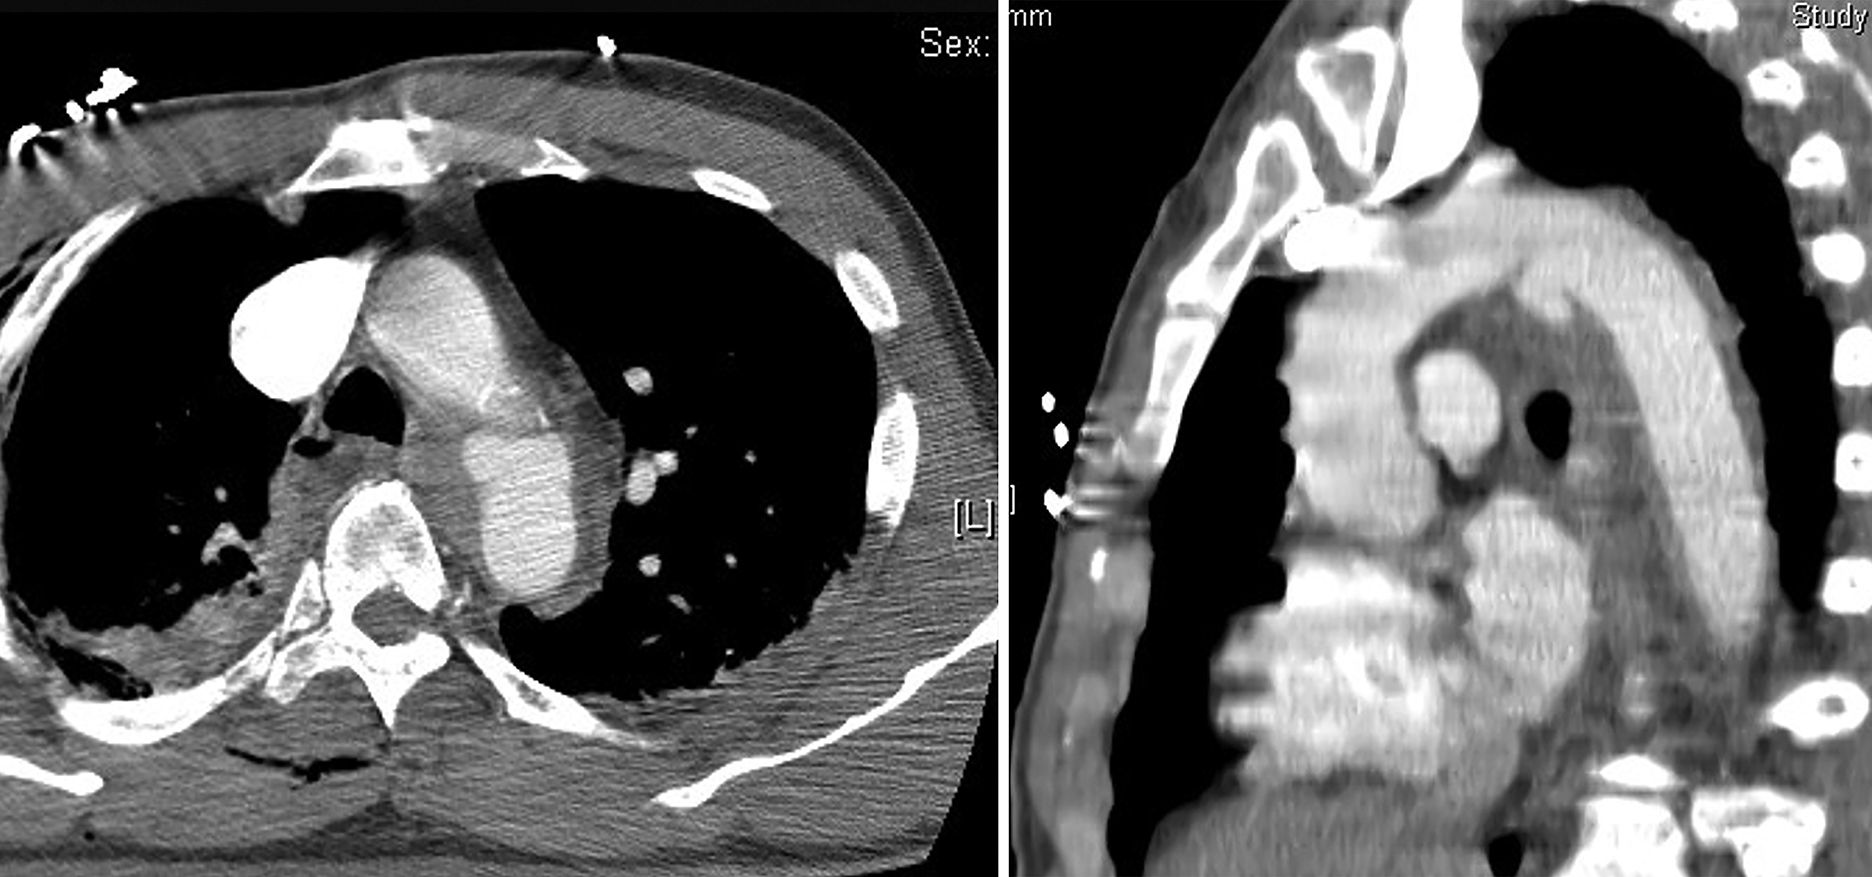

Computed tomography angiography (CTA) is an essential screening test and is considered the “gold standard” diagnostic imaging modality to detect aortic injury in patients with trauma. CTA of the entire body takes only 5 minutes. Thus, in patients who are hemodynamically stable, especially after high-impact BTAI, CTA is highly recommended. CTA has largely replaced conventional angiography and transesophageal echocardiography (TEE) as the screening modality of choice for the diagnosis of TAI in hemodynamically stable patients due to its availability, high sensitivity, and relatively rapid and less-invasive nature. At many trauma centers, CTA of the thorax is usually integrated into a whole-body CT “trauma pan-scan,” an approach that has been shown to improve survival and reduce imaging time. The reported sensitivity of CTA is between 86% to 100%, with specificity of 40% to 100% and negative predictive value of 85% to 100%, , indicating that few patients with TAI will be missed. Unfortunately, false positives, or patients diagnosed with TAI based on CTA who do not actually have an aortic injury, can be high with this test (with specificity as low as 40% and positive predictive value as high as 15%) ( Fig. 24.5 ). Confirmatory tests with high specificity, such as aortography, intravascular ultrasound (IVUS), or TEE, may be necessary in patients with an equivocal diagnosis. , , ,

While considered the “gold standard” in imaging for TAI, CTA can produce false positives, with specificity as low as 40% and positive predictive value as high as 15%.

The CTA findings of TAI can be divided into direct signs of injury and indirect or associated findings. Direct findings of an aortic injury noted on CTA include the presence of an intimal flap, an intramural hematoma, a pseudoaneurysm, and active extravasation of contrast media. Injuries that only involve the intima, classified radiologically as minimal aortic injuries, should only have direct findings of TAI. Minimal aortic injuries can present with an intimal flap, an intraluminal aortic thrombus, or an intramural hematoma. With the improvement in technology allowing thinner CT slice thickness, minimal aortic injuries are being diagnosed more frequently. More severe injuries often have both direct and indirect findings of TAI. Indirect signs include the presence of a periaortic hematoma, change in aortic caliber, and irregular aortic contour. Direct signs of aortic injuries were more accurate diagnostically than indirect signs.

Multiple normal anatomic variants and conditions can mimic an acute TAI. Ductal remnants, a diverticulum or small bump, are normal remnants of the embryologic ductus arteriosus. Ductal remnants are typically smooth-walled and have obtuse margins that are continuous with the aortic wall and are often calcified ( Fig. 24.6 ).

Multiple anatomic variants can mimic an acute TAI. Ductal remnants, a diverticulum or small bump, are normal remnants of the embryologic ductus arteriosus. Typically smooth walled, ductal remnants (arrow) have obtuse margins that are continuous with the aortic wall and often calcified.

In contrast, the typical pseudoaneurysm forms an irregular outpouching from the lumen, displaying acute margins and intimal irregularity at its base. Another variant that might mimic aortic injury is the aortic spindle, which is a narrow and dilated area of the aorta between the left subclavian and the ductus arteriosus. Infundibula can have a similar appearance to a ductal remnant but are found at the origin of bronchial or intercostal arteries and can also be confused with a small pseudoaneurysm. Infundibula are typically cone-shaped and smooth-walled, with a small artery extending from the apex. However, in all these normal variants, the contour is smooth and regular without intimal irregularities. If a definitive diagnosis is in question, other specific imaging modalities, such as TEE, are helpful to eliminate any confusion and confirm the diagnosis.